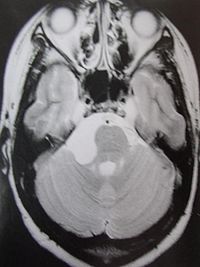

2.MR表现:

①鞍上池或桥小脑角池类圆形或不规则病变,边缘锐利。

②T1加权绝大部分为均匀的低信号,少数由于瘤体内含液态胆固醇或出血而呈高信号影。T2加权呈明显的、均匀一致的高信号影,高于脑脊液信号。

③肿瘤包膜于T1加权呈中等信号,T2加权呈高信号影。

④增强检查无强化效应。